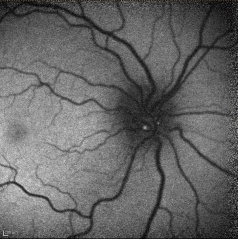

Red-Free Photography

Red-free photography may reveal autofluorescence of the drusen without the administration of fluorescein. Alterations in the peripapillary retinal nerve fiber layer may include varying degrees of regional thinning, especially nasally, or diffuse loss of NFL. Deep or buried ONHD tend not to show any NFL changes on red-free photography, possibly due to the attenuation from the overlying tissue.